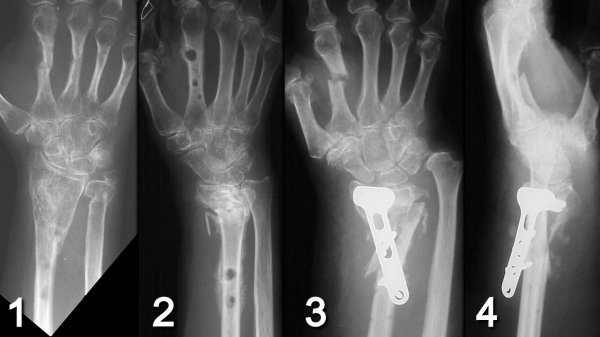

Figure Legend: Complications of external

fixation. External fixers used for distal radius fracture fixation

may result in sensory nerve injury and symptomatic neuroma, pin tract infections,

osteomyelitis and fracture through the pin site. (1) Healed index

of metacarpal fracture following external fixation in a patient with osteogenesis

imperfecta. (2) Pin loosening and periosteal reaction in another

patient. (3,4) Index metacarpal fracture through pin site and complete

loss of reduction in another patient.